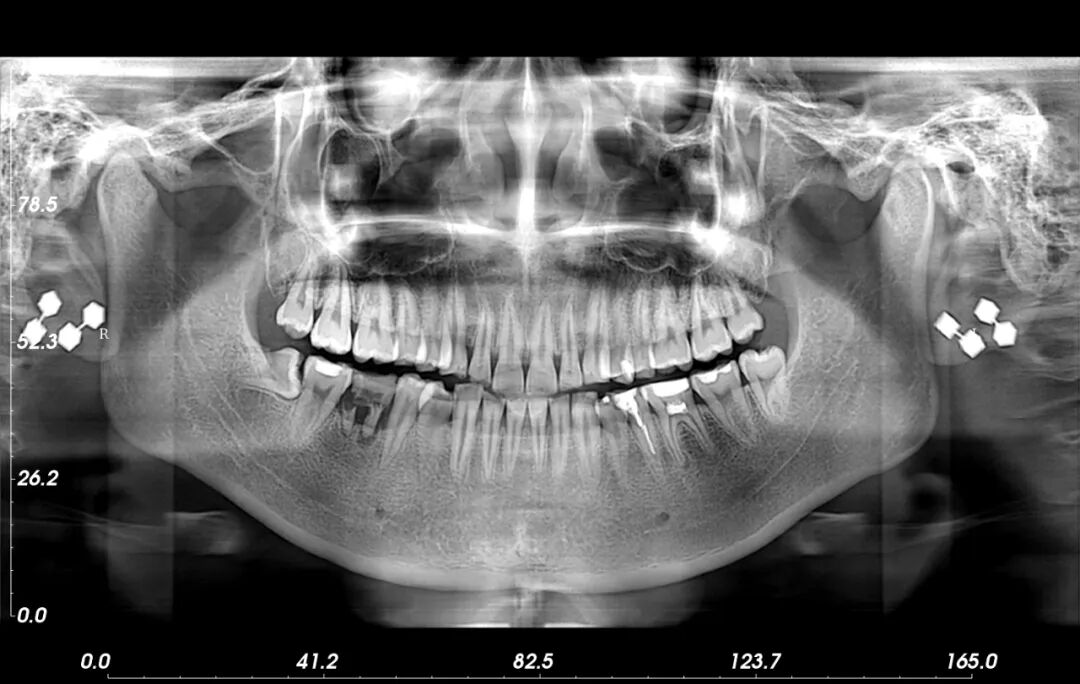

自长城医院于2022年9月底购置一台口腔CT(三合一CBCT,即锥体束CT)投入使用后,受到本市及周边人民群众的认可,截止2023年2月20日,共检查932人次,极大促进了口腔疾病的诊断准确率,推进我院医疗水平整体提高。

口腔科主任李哲介绍说:“我们整理了日常需要进行口腔CT检查的疾病分类:成人牙周炎、牙髓炎、根尖炎、多生牙和阻生牙拔除,根管治疗、种植牙等都会用到口腔CT检查,孩子乳牙滞留、齿萌也会用,能得到患者的认可源自于口腔CT检查结果:直观、清晰,方便与患者有效沟通,能得到更好的诊疗效果,而且价格低廉,可刷医保,更能被广大群众接受。

口腔CT的优势:三合一CBCT是一种专门针对口腔额面部特点设计的X射线成像系统,又称为数字化容积X线断层摄影术。锥形束CT(cone beam computed tomography, CBCT),其工作原理是应用圆锥形二维平板探测器,围绕被探测区域做360度旋转获得系列二维影像,通过特殊算法得到三维立体影像,它能够从矢状位、冠状位和轴位三维角度清晰地显现额面部位的组织结构和病变组织状况,真实反映颌面部的三维结构。

相对传统的多排螺旋CT而言,CBCT有着更为明显的优势。CBCT具有精确度更高、放射剂量低、扫描时间短、空间分辨率高、对患者体位要求低等明显的优点。特别是在牙科疾病诊治过程中,具有高度的精确性。可以精确测量出牙槽骨各个部位的高度和厚度,对于正畸风险评估、方案选择有重要的指导意义,对牙周及种植治疗也具有极高的参考价值,在很大程度上弥补了传统CT在牙科疾病诊断中的不足。